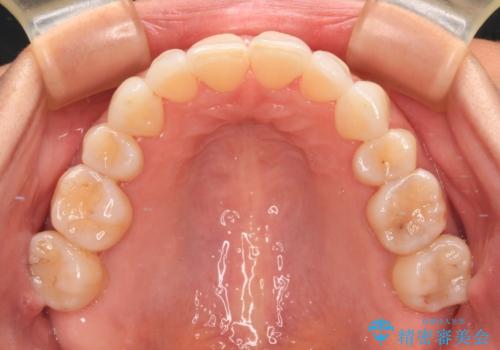

- 上の前歯の出っ歯を治したいとのことで来院された患者様です。

後戻りによる再矯正というもともあり、インビザラインを希望されていました。

上顎の歯は後方移動とIPR(歯と歯の間を削る)によって口元が引っ込むように、下顎は歯列全体の拡大とIPRによって上顎とバランスよく咬み合うように設計し、インビザラインにより治療を行うこととしました。

治療を開始して暫くして、勤務先から2年以上帰国することができず、それまでの移動がほとんど後戻りしてしまい、帰国後に再度後戻りをリカバリーするための治療を行うこととなりました。

5年以上の治療期間がかかりましたが、気になっている部分を改善することができました。